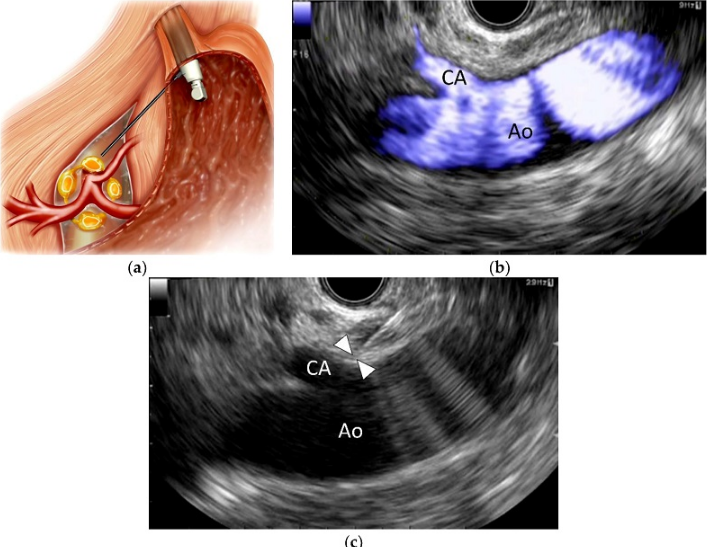

Nội soi dạ dày khác với siêu âm nội soi dạ dày. Nội soi dạ dày là kỹ thuật sử dụng một ống mềm có gắn camera đưa vào ống tiêu hóa, qua đó bác sĩ quan sát tổn thương và đánh giá tổn thương trên bề mặt. Vậy để phát hiện những tổn thương phía dưới bề mặt của ống tiêu hóa, bác sĩ dùng phương pháp nào? Trước vấn đề này, các nhà khoa học đã cho ra đời ống nội soi tích hợp đầu dò siêu âm tần số lớn. Đây gọi là kỹ thuật siêu âm nội soi (EUS)

Siêu âm nội soi là sự kết hợp giữa kỹ thuật siêu âm và nội soi. Khi đầu ống nội soi tì vào niêm mạc đường tiêu hóa theo các vị trí giải phẫu thích phù hoặc soi trực tiếp vào vùng tổn thương sẽ giúp xác định mức độ tổn thương, tổn thương xuất phát từ lớp nào, tình trạng xâm lấn xung quanh, xuất hiện hạch.

Trong quá trình nội soi siêu âm, bác sĩ sẽ đưa qua miệng một ống nội soi nhỏ, mỏng, mềm dẻo, sau đó đưa vào đường tiêu hóa, đầu dò tích hợp ở đầu ống nội soi sẽ tạo ra sóng âm thanh và ghi nhận hình ảnh chính xác các vùng mô xung quanh, gồm cả mạch bạch huyết. Sau khi nội soi ở vị trí đã xác định, bác sĩ rút dần ống nội soi. Quá trình nội soi thường kéo dài từ 30 đến 90 phút.

Hiện có đầu dò siêu âm tròn có thể phóng âm thanh vòng tròn và đầu dò siêu âm dẹt có thể siêu âm khu trú theo một hướng.